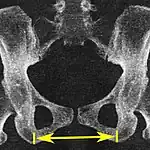

| Interspinous distance | ![]() |

![]() Axial plane |

The line between the closest bone points of the ischial spines | 9.5 to 11.5 cm.[6] | |